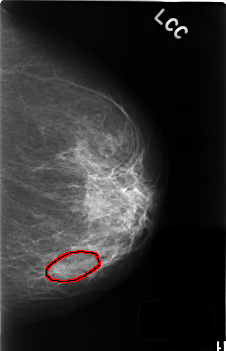

C_0405_1.LEFT_CC

LEFT_CC LINES 4552 PIXELS_PER_LINE 2928 BITS_PER_PIXEL 12 RESOLUTION 50 OVERLAY

FILE: C_0405_1.LEFT_CC.OVERLAY

TOTAL_ABNORMALITIES 1

ABNORMALITY 1

LESION_TYPE CALCIFICATION TYPE AMORPHOUS DISTRIBUTION SEGMENTAL

ASSESSMENT 4

SUBTLETY 2

PATHOLOGY BENIGN

TOTAL_OUTLINES 1

BOUNDARY